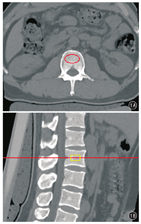

将CT扫描数据传至定量CT PRO工作站,测量C2~C7、L2~L4各椎体的vBMD:采用美国Mindways定量CT PRO 5.0.3软件,进入"New 3D spine exam anylasis"模块,读取志愿者的影像图像。在横断面图像中,选定要测量椎体松质骨中央椭圆形区域的中心为测量区域,避开皮质骨、椎静脉丛及骨岛,确定ROI(图1A);在矢状位图像中,将椎体方向调整至与水平参考线平行,由软件自动得到该区域的vBMD(图1B)。由2名有3年以上放射科工作经验并经过骨密度测量培训的医师分别独立完成各志愿者颈椎及腰椎vBMD测量,测量结果取平均值。